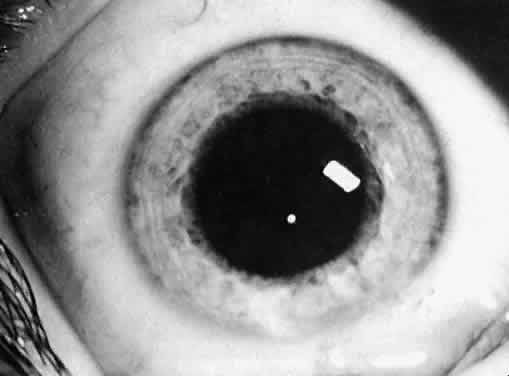

Not all cataracts require surgical treatment. Eyes with punctate or small anterior polar cataracts and others with partial opacification of the lens, such as posterior lenticonus, which only slightly interferes with the refraction of light, are best followed and not surgically treated (Fig. 1). In some cases, it is difficult to determine whether the presence of a partial cataract is responsible for a decrease in visual acuity or whether the refractive error or optical distortion produced by the cataract has produced a mild, reversible form of deprivation amblyopia. In these situations, correction of the refractive error and a trial of occlusion therapy should be attempted. If the visual acuity improves, it may be deduced that amblyopia was responsible for the loss of visual acuity and that the optical distortion produced by the partial cataract is not yet surgically significant.

Usually, anterior polar cataracts are visually insignificant and allow normal visual development (see Fig. 1). However, some affect vision, and all require careful monitoring.7 Centrally located cataracts that are on or near the posterior lens capsule have a greater effect on the refraction of light and visual acuity (Fig. 2). Nuclear cataracts associated with metabolic disorders or prenatal infections produce double refracting systems that cause optical distortion and significantly decrease visual acuity (Fig. 3).